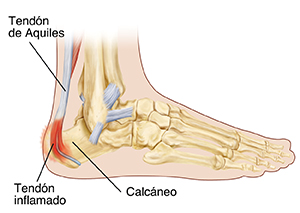

A su hijo le diagnosticaron la enfermedad de Sever. Es una irritación en la zona donde el tendón de Aquiles se une con el talón (hueso calcáneo). La presión constante que ejerce el tendón de Aquiles hace que la zona se inflame. Esta afección es dolorosa. Pero con los cuidados adecuados, se puede tratar.